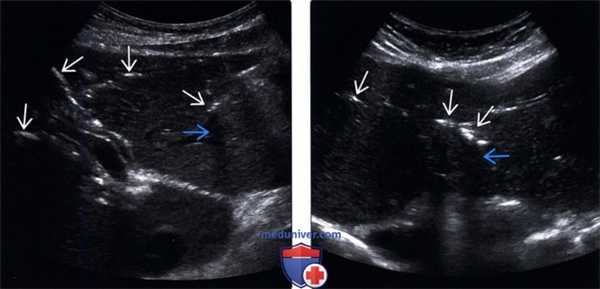

(Левый) На поперечном УЗ срезе через левую долю печени по ходу желчных протоков определяются множественные линейные эхогенные зоны, некоторые из них отбрасывают акустическую тень; такая картина отражает наличие газа в желчных протоках.

(Правый) На поперечном УЗ срезе через левую долю печени визуализируются линейные эхогенные очаги, отбрасывающие «грязную» акустическую тень; такие изменения вызваны наличием газа во внутрипеченочных желчных протоках.